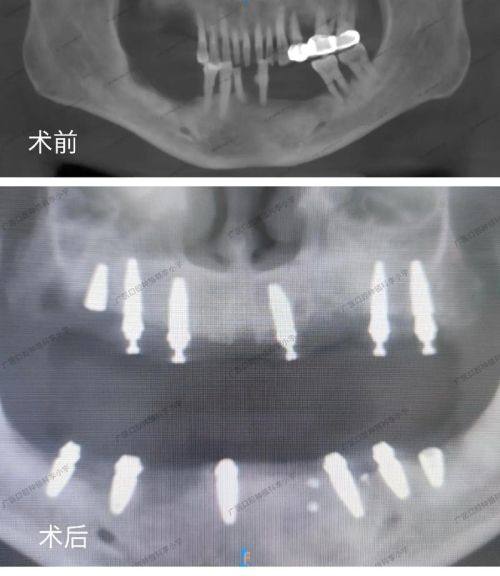

All-on-X即刻负重、美学种植等高难度复杂种植项目:可实现种植体即刻负重,减少就诊次数,同时兼顾口腔美学成效,针对复杂缺牙情况提供个性化的种植解决方案。

患者王阿姨 种植修复项目“缺牙好几年,吃饭都受影响,杨医生为我做了All-on-X即刻种植,当天就能正常进食,修复速度比预期好特别多,现在终于能安心吃饭了,医生技术真的特别靠谱。”